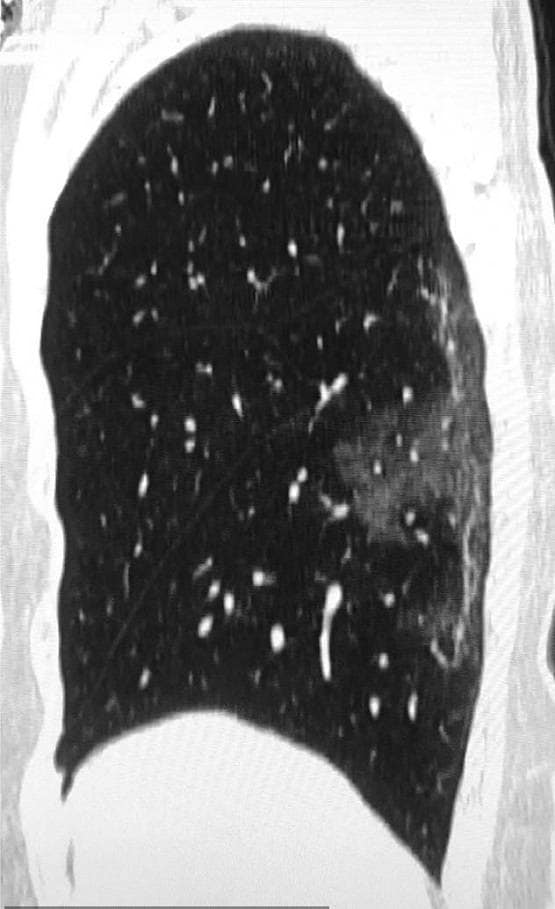

हेल्थ एक्स्पर्ट्स का कहना है कि कोरोना वायरस से फेफड़ों में पड़ने वाले सफेद धब्बे बिल्कुल वैसे ही हैं जैसे SARS और MERS से पीड़ित रोगियों के शरीर में दिखाई दिए थे.

साल नवंबर 2002 से 2003 तक SARS ने करीब 8,000 लोगों को अपना शिकार बनाया था जिसें से 774 की मौत हो गई थी.